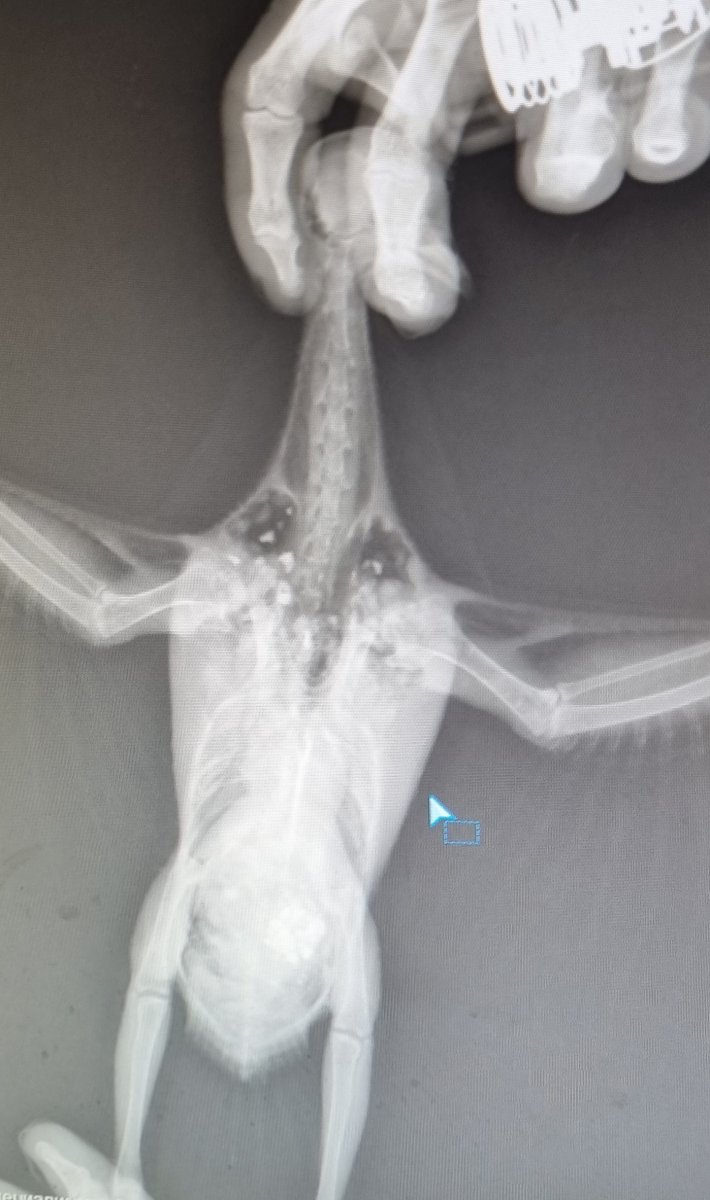

Зравствуйте. Переделали ренген. Помет при отмене всех лекарств лучше. Но картина на ренгене нет

20221009_124542.jpg

20221009_124621.jpg

но сейчас я сделала латеральную проекцию.

да, почки сильно не в порядке.

и голова, и хвост- очень яркие.

714019041_.thumb.png.ee30528b9ae2623773cfe7b526d9c343.png